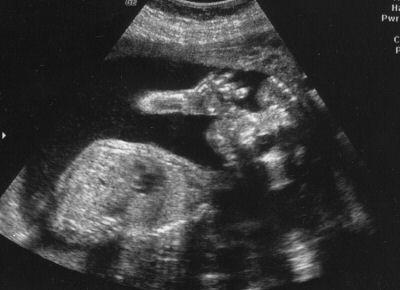

15 haftalık bebek Bebeğinizin kemikleri iyice sertleşmesine rağmen, derisi hala çok ince ve deri altından damarları görünüyor. Kafa derisi üzerinde ince ve ipeksi tüyler belirginleşmeye başladı. 12 cm’lik koca bir bebek olarak, artık yüz ifadeleri bile var.